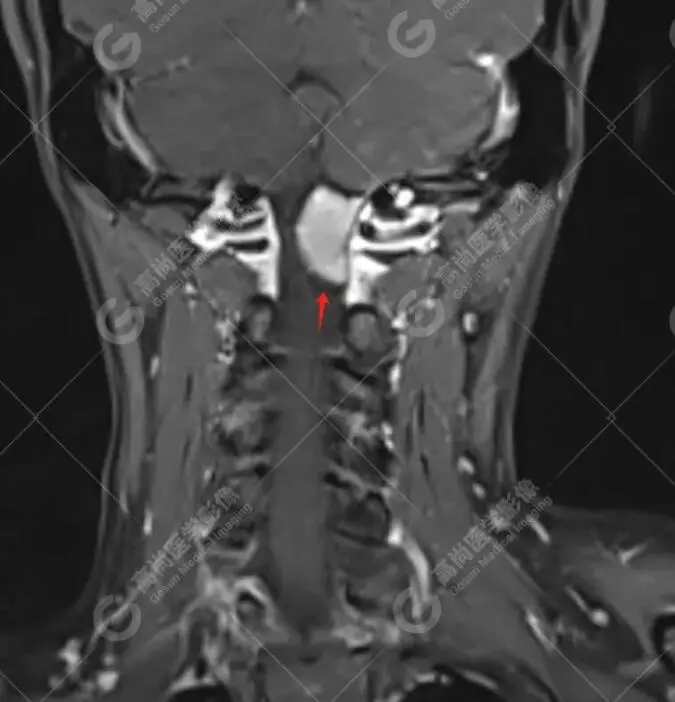

林女士,40岁,左侧头颈部疼痛1年,一直以为只是偏头痛,药物治疗,但效果甚微。后来到我中心做了头颅磁共振平扫;颈椎磁共振平扫+增强,终于发现症结所在。

磁共振图像

T1压脂增强冠状位

检查所见:检查发现其C1椎体-向上枕大孔上部水平椎管髓外硬膜下占位,考虑是脊膜瘤。

T1WI多为等信号或低信号,T2WI多为等信号或稍高信号,钙化显著时信号不均质;增强扫描多呈明显均匀强化,部分可见特征性的“硬膜尾征。